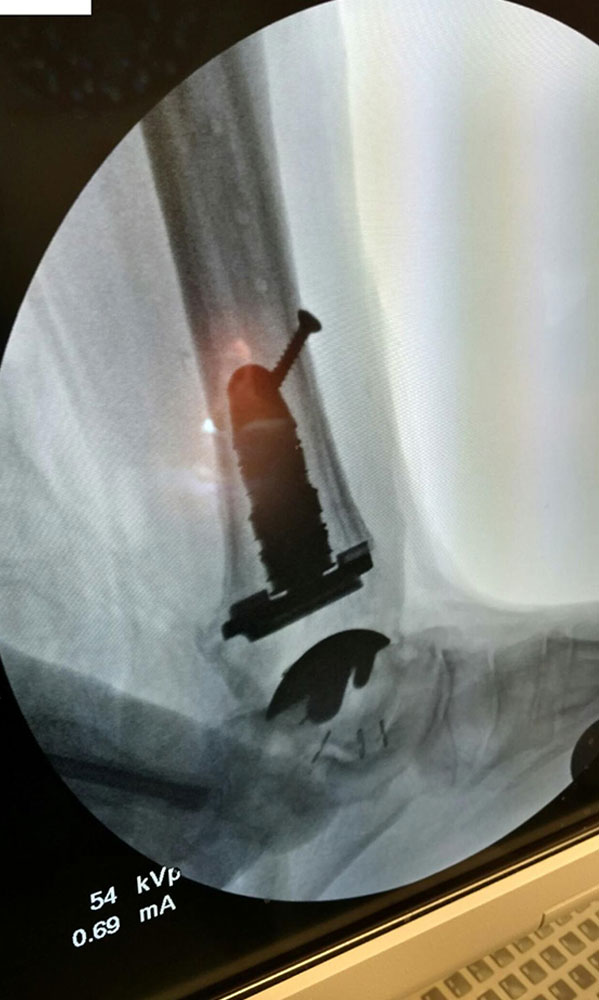

"Surgical misadventure" by another surgeon about 8 years ago. The wrong fixation was used for a flatfoot repair, & the deformity was not corrected. Patient came in with severe foot & ankle pain, with no arch at all. She was unable to play with her grandchild because the pain was so bad, & because she felt unsteady. The old hardware was removed, a lateral calcaneal lengthening osteotomy was performed along with a medial column/1st ray realignment. The ankle was painfully arthritic, & patient elected a total ankle replacement vs. an ankle fusion. She is now able to walk pain free & play with her grandchildren!

Ten years of severe ankle pain with a mal-positioned ankle fusion is now relieved! Patient is now walking with pain-free ankle motion!